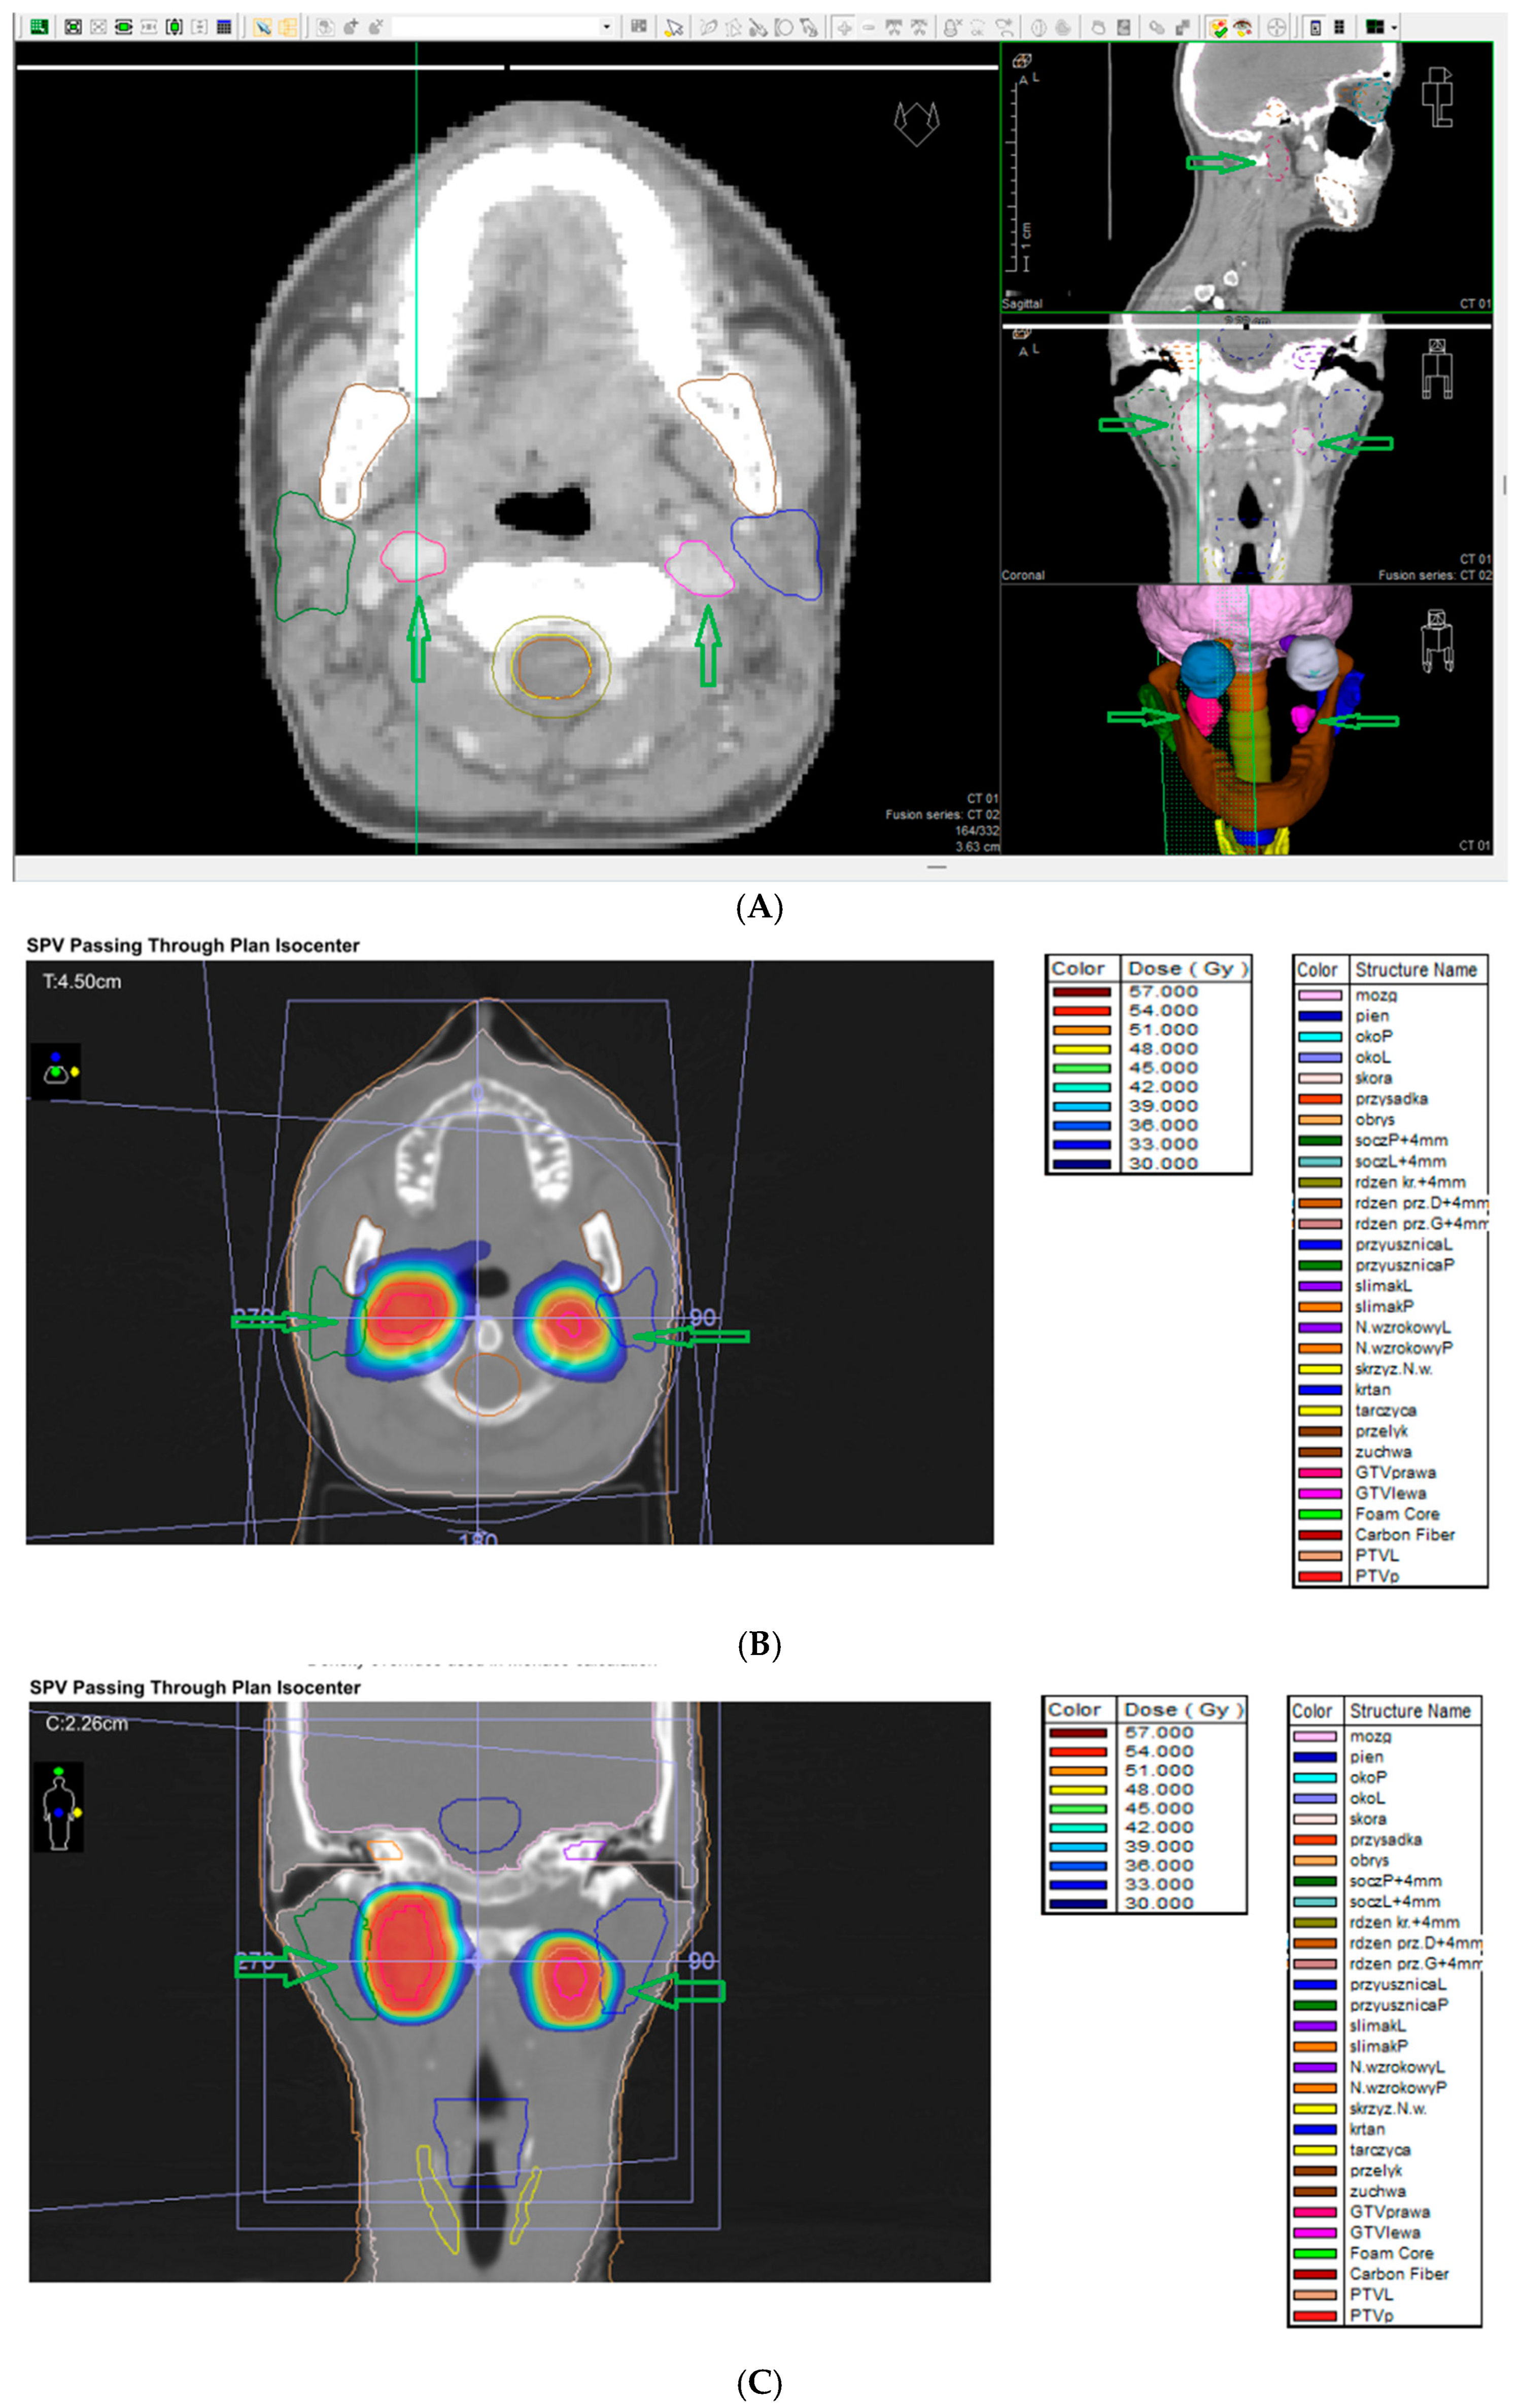

7.9. External Beam Radiotherapy (ERBT) and Hypofractionated Stereotactic Radiotherapy (hSRT)